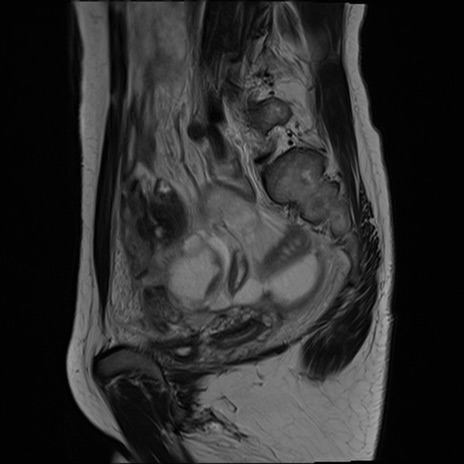

症例39 T2WI(矢状断像)

MRI(4日後)